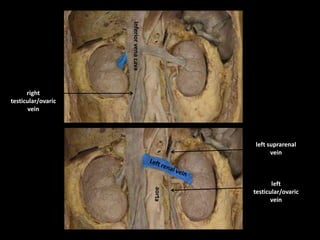

left suprarenal

vein

left

testicular/ovaric

right

Inferior

vena

cava